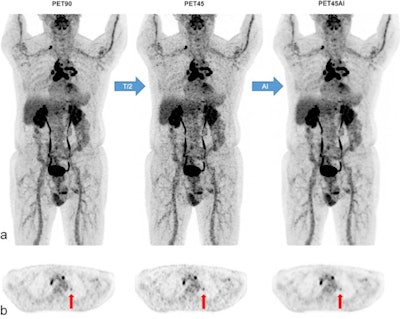

Next, the researchers performed two PET reconstructions: one for routine clinical purposes using the full acquisition time of 90 seconds per bed position ("PET90"), and a second one using 45 seconds per bed position ("PET45AI"), with reconstruction performed by the algorithm.

Five experienced nuclear medicine physicians reviewed the PET90 and PET45AI images side-by-side, and attributed a global, whole-image quality score to each PET series (1 = poor; 2 = moderate; 3 = good), as well as evaluated cancer lesion detectability.

According to the results, image quality scores were similar between original PET90 and PET45AI, with both receiving good scores in 92% of exams and moderate scores in 8% of exams.

Concerning lesion detection, 33 out of 195 patients presented a normal and concordant examination on both PET series. In the remaining 162 patients, a total of 856 lesions were detected. Of these 856 lesions, the reviewers visualized 836 lesions in both original PET90 and denoised PET45AI scans, which resulted in a lesion concordance rate of 97.7%.

"AI allows F-18 FDG-PET duration in digital PET/CT to be halved, while restoring degraded half-duration PET image quality," the researchers wrote.